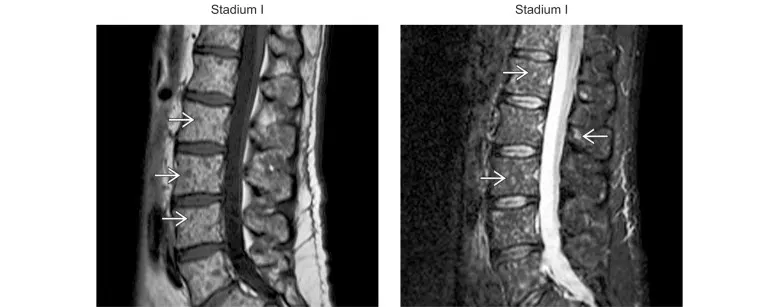

Types de MO normal et micronodulaire : Associés à la maladie au stade I

(Gauche) L’IRM T1 sagittale à travers la colonne lombaire montre le remplacement de la graisse de la moelle asseuse normale par des foyers micronodulaires (→) de faible signal T1, ce qui correspond à l’infiltration par un myélome. (Droite) L’IRM STIR sagittale à travers la colonne lombaire montre des foyers micronodulaires (→) de signal STIR accru. L’infiltration micronodulaire correspond au stade I de la maladie (PLUS de Durie et Salmon), qui peut aussi présenter une moelle avec graisse normale.